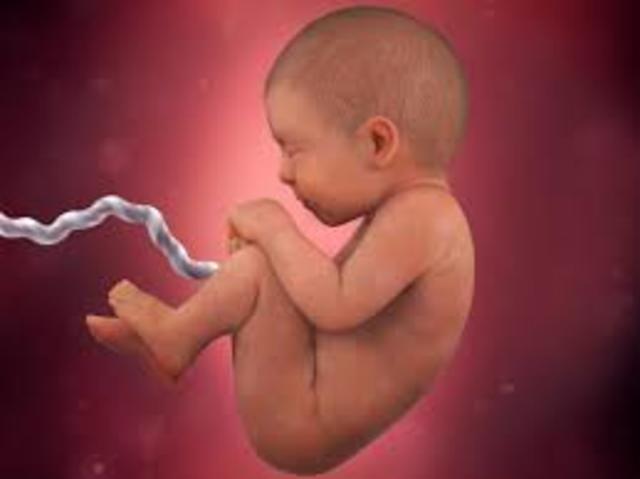

• 3rd Trimester

Length of Time: 28-40 weeks.

• 7th Month

7th Month

1. The baby can cry.

2. The baby can suck their thumb.

3. The baby can open their eyes.

• 8th Month

8th Month

1. The baby gains 2-3 pounds.

2. The baby moves their head into the down position.

3. The baby's lungs are fully developed.